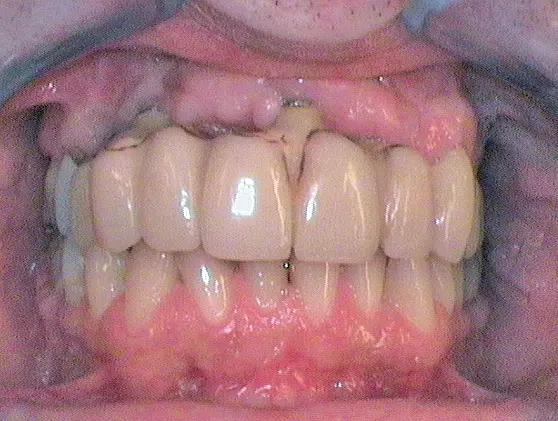

Nach Freilegung der Implantate regio 026,027 im Februar 2020, bei der auch die Implantation regio 037 (T3, Zimmer Biomet Dental, 4,0 mm x 13,0 mm) vorgenommen wurde (Abb. 32 OPG nach Freilegung), erfolgte im März nach Abformung mit offenem Löffel (open tray technique) und Gesichtsbogenregistrat die prothetische Versorgung mittels CAD/CAM gefräster Abutments (Dentaltechnik Hessel und Lutgen, Trier) und transversal verschraubter, verblockter VMK-Kronen (Abb. 33-36). Die Freilegung und Versorgung des Implantates 037 ist zusammen mit der Entfernung des Zahnes 38 für Juli 2020 geplant.